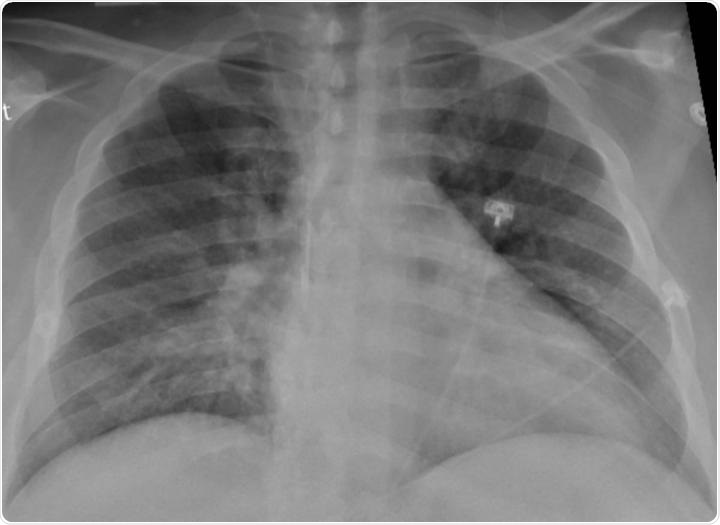

Chest X-ray of a SARS-CoV-2-positive patient exhibiting confusion and showing weakness on his left side shows pneumonia in the lower lungs.

Image Credit: Radiological Society of North America